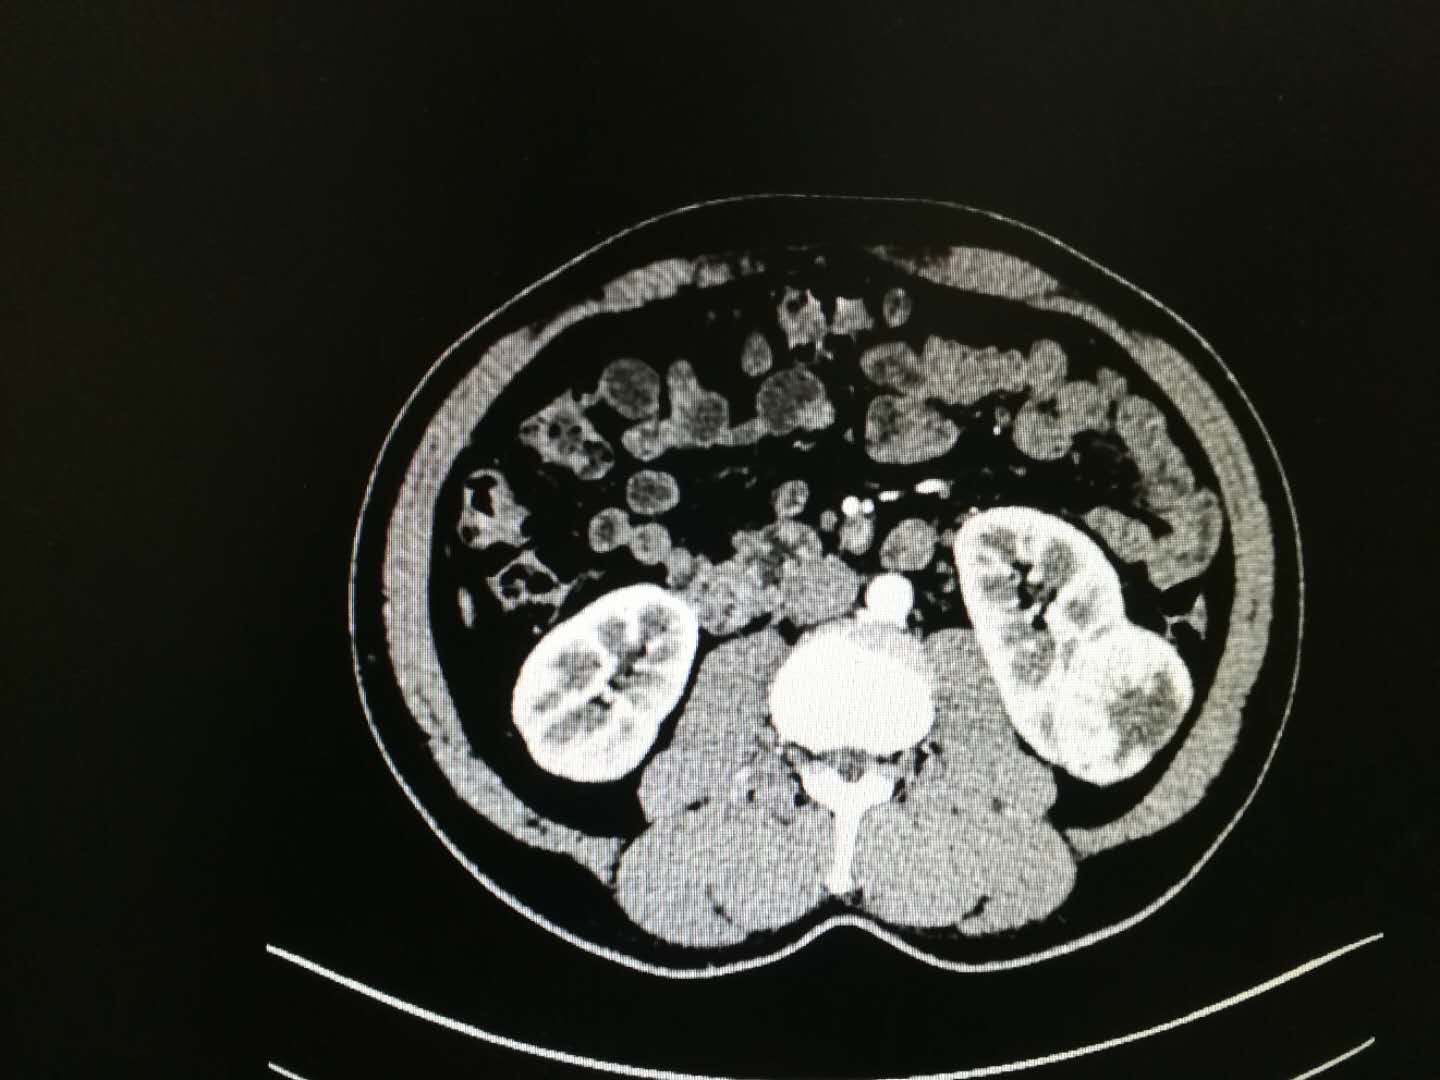

主诉:体检发现左肾占位9天

现病史:患者于入院前9天外院体检B超发现左肾占位,大小约44*42mm,无左侧腰部酸胀感,否认尿频尿急尿痛排尿困难,夜尿增多,血尿症状,无发热寒战恶心呕吐腹痛等不适,为进一步治疗,来我院门诊就诊,门诊查CT,左肾占位,考虑恶性肿瘤可能大,故拟“左肾占位”收治入院

诊断:左肾占位

治疗:患者入院后完善相关检查,全麻下行左肾切除术,术顺安返,术后予头孢,复方谷氨酰胺肠溶胶囊等对症支持治疗,现患者一般情况可,予以出院